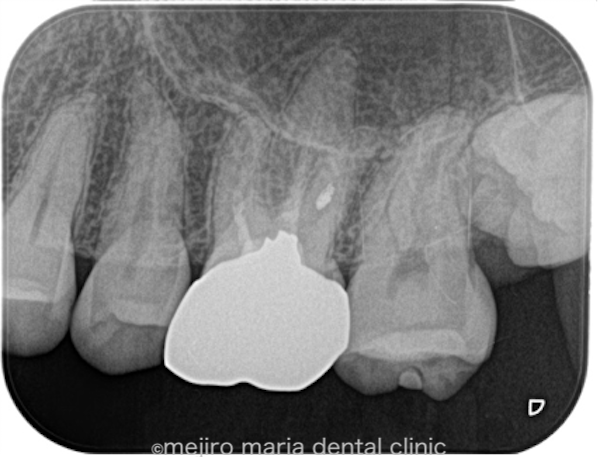

左上6番(上顎左側第2大臼歯)は既に根管治療が施されており、根尖性歯周炎は根尖に確認されないものの、以前の治療の質は良い状態ではない(質が低い)ことが予想できます。根管治療の質を高める意味合いで再根管治療をご提案させていただきました。